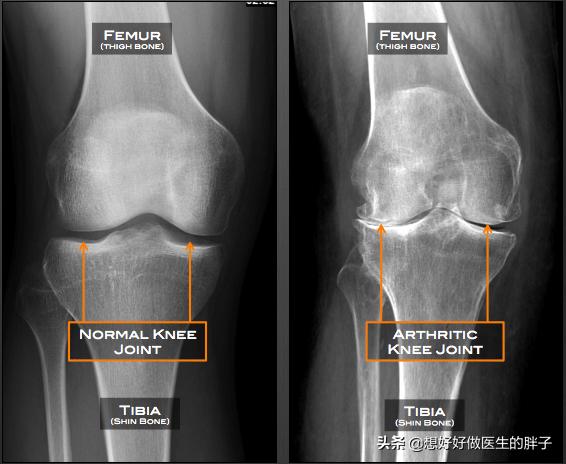

●Examen radiographique de l'articulation du genouLa radiographie du genou permet de déterminer si le patient souffre d'une ostéoporose importante et s'il y a un rétrécissement important de l'espace articulaire.l'arthroseL'existence de laPolyarthrite rhumatoïde.Ou tout autre problème de genou courant.

Comme vous pouvez le voir sur la photo ci-dessous, les articulations se sont typiquement développéesLacunes visibles, formation osseuse réduite, ostéoporose des articulations plus lourdesSi un tel patient présente des sensations et des douleurs anormales évidentes, l'injection intra-articulaire de vitrate de sodium ou l'administration constante d'analgésiques par voie orale le feront souffrir énormément, ce qui ne l'aidera pas vraiment à résoudre le problème.

La plus courante est l'arthrose du genou, qui est principalement causée par des changements dégénératifs du cartilage articulaire et des ostéophytes secondaires. Le principal symptôme de cette maladie est une douleur dans l'articulation du genou, qui s'aggrave avec l'activité et s'améliore avec le repos. La zone autour de l'articulation est froide et il est souvent nécessaire de porter des genouillères pour la maintenir au chaud. Gonflement et limitation des mouvements. Dans les cas graves, on observe une inversion du genou ou une déformation en valgus.

Si vous avez froid aux genoux, il peut s'agir de "vieilles jambes froides" ; si vous ressentez une douleur au genou, il peut s'agir d'arthrite ; si l'étirement du genou est sonore, il peut s'agir d'une blessure au genou. Lorsque ces trois situations se produisent en même temps, les personnes d'âge moyen et les personnes âgées doivent redoubler de vigilance à l'égard de l'arthrose du genou, qui est souvent désignée par l'expression "changements dégénératifs dans l'articulation du genou".

- fricatif--Lorsque le cartilage articulaire est très usé, les extrémités des os sous-chondraux perdent la protection du cartilage et le frottement direct émet un bruit de frottement faible et rauque ; les débris de cartilage qui se promènent dans la cavité articulaire provoquent aussi facilement des blocages, ce qui donne lieu à un bruit de frottement articulaire. Les patients doivent faire la distinction avec le claquement physiologique normal, les critères de jugement sont très simples, le claquement pathologique est souvent accompagné de symptômes d'inconfort articulaire.